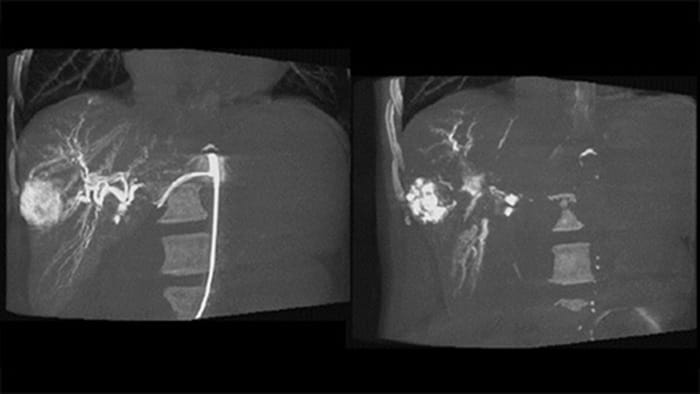

Dual View ermöglicht die gleichzeitige Darstellung von zwei CBCT-Datensätzen. Sowohl die arterielle als auch die postarterielle Phase können nebeneinander oder in einer fusionierten Überlagerungsansicht angezeigt werden.

Dual View ermöglicht die gleichzeitige Darstellung eines 3D-Bildes der arteriellen Phase vor der Embolisation und eines Bildes nach der Embolisation zur Bestimmung des Behandlungsendpunkts.